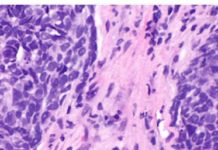

What Cancer Therapy Is Teaching Us About The Vast Complexity Of The Human Condition

How can immunotherapy cure a 65-year-old, newly retired man of Stage IV lung cancer, restoring the promise of his golden years with his family,...